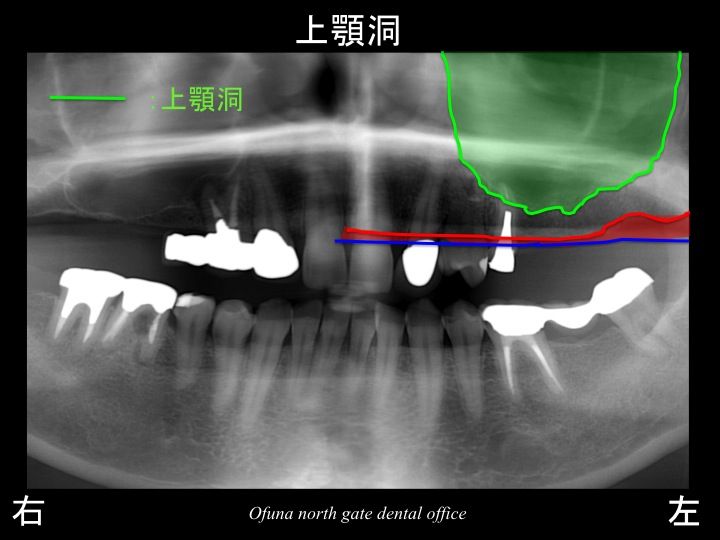

次に上顎洞という空洞を見てみましょう!

以下のレントゲンの緑線は上顎洞という空洞です。

骨ではなく、穴が開いているのです。

さらに分かりやすくするために

上顎洞を緑色で塗ってみましょう!

骨の高さが非常に少なくなっているのが分かるかと思います。

このままであるとインプラント治療は難しくなります。

短いインプラントしか埋入するこができません。

短いインプラントの予後は明らかに悪いのです。

しかし、今回の症例では、4〜5ミリ程度の骨の高さしか存在していません。

通常今回の症例のように上顎の奥歯に骨吸収が大きい場合(骨の高さが5ミリ以下)には、

上顎洞の中に骨移植を行います。

こうした治療法をサイナスリフト法(上顎洞底挙上術) と言います。